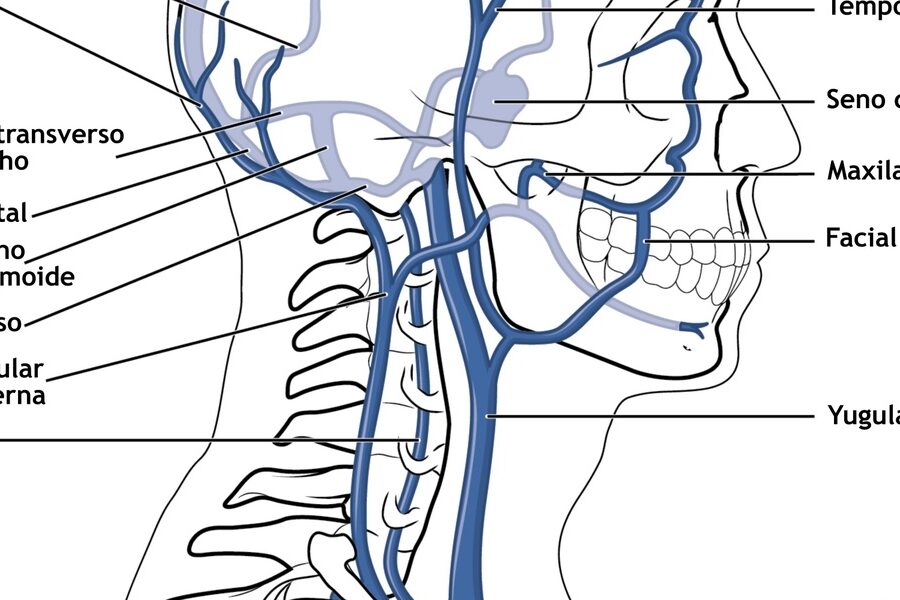

3. Lungs have a specialized blood supply that maximizes gas exchange

Blood reaches the lungs through two systems: the pulmonary arteries carry deoxygenated blood from the right ventricle to the alveolar capillaries for gas exchange, while the bronchial circulation supplies airway tissues with nutrients.

The pulmonary capillary network is extremely dense, minimizing the distance oxygen must diffuse into blood. That geometry is why even small changes—fluid in the alveoli (pulmonary edema) or blocked vessels (pulmonary embolism)—can sharply reduce oxygen uptake.

Clinically, a pulmonary embolism can cause sudden shortness of breath and low oxygen levels; diagnosis and treatment often involve imaging and anticoagulation or surgical intervention in severe cases.